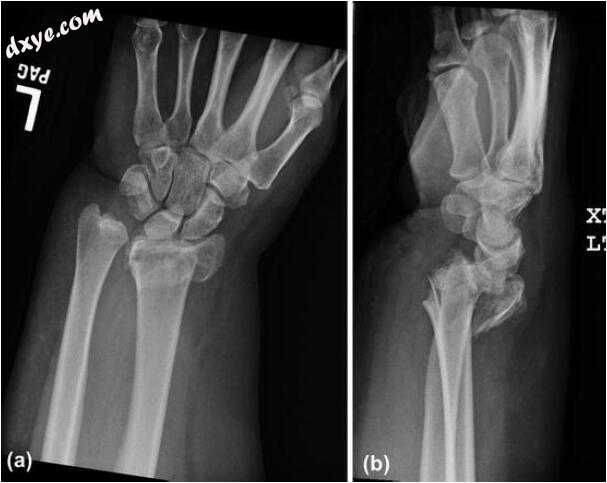

一名37岁的右手显性病态肥胖女性患有阻塞性睡眠呼吸暂停和哮喘病史,曾参与机动车事故。她持续右侧开放性胫骨干骨折,伴有胸骨后血肿的胫骨骨折和左侧闭合的桡骨远端骨折(图11.1)。她出现正中神经分布麻木和刺痛,随着桡骨骨折的闭合复位而改善。根据她的病史,她被发现有与腕管综合症一致的伤前症状。在进入1级创伤中心后,她对胫骨开放性骨折进行了冲洗、清创和髓内钉固定,并对其桡骨远端骨折进行了复位和夹板固定。第二天,她回到手术室,确定了桡骨远端骨折的最终固定方法。鉴于她的下肢损伤和需要立即负重上肢进行早期活动,她采用开口复位和桡骨远端骨折内固定,背侧跨越桥板,辅助桡骨茎突克氏针固定(图11.2)。在固定桡骨骨折后,她进行了开放的腕管松解。远端测试了桡尺骨关节的稳定性,发现它是稳定的;然后将她放在轻微旋后的钳夹板中。她被允许立即通过前臂对受伤的肢体施加压力以进行转移和操作。十二周后,桡骨骨折在X光片上愈合后,她回到手术室,取出背桥板和克氏针。 (图11.3和11.4)将她放入柔软的敷料中,术后不受限制。

1.jpg

图11.1损伤射线照片。(a)正视图和(b)侧视图